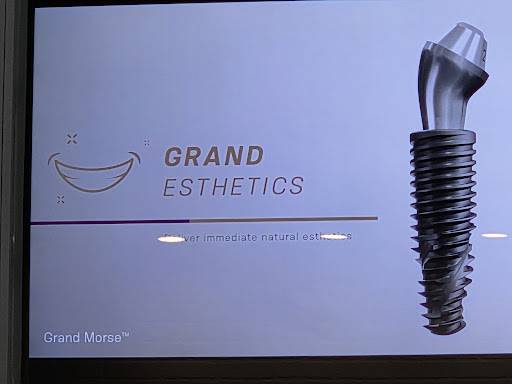

Neodent Implant Placement

Price Varies 60 minutesNeodent implant is the best solution when a tooth is missing, it returns the function an sthetics similar as the original tooth.Book Quick view -